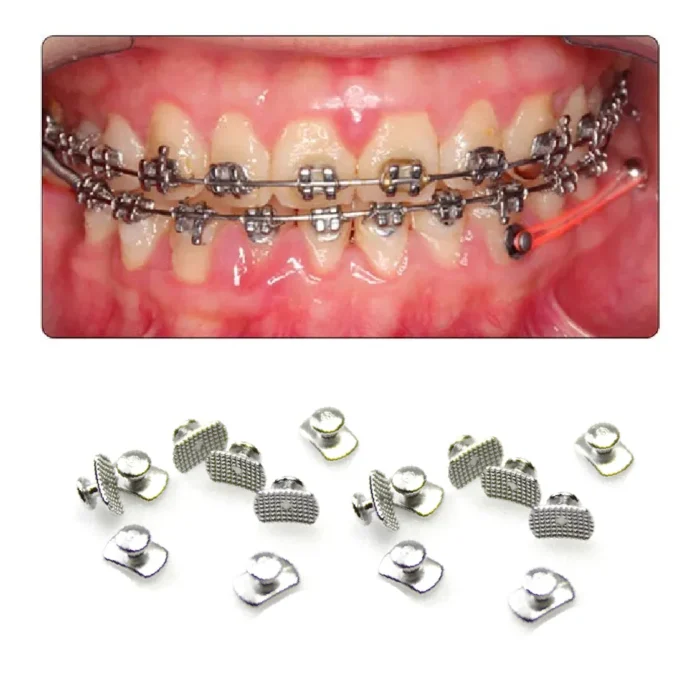

Ortho Direct Lingual Buttons are made of high quality stainless steel. It’s a common button in all the dental procedures. Concave bondable lingual buttons are used in dental movements such as retractions, rotations, pull and anchoring systems. This retains the elastic, wires, chains and ligatures.

Lingual buttons are used in many instances for labial, as well as lingual orthodontics. Also aids in the seating and positioning of band as well as accepting maxillary and mandibular appliances such as palatal bars and quad helix appliances.

- The application of elastics

- Crossbite correction

- Bonding impacted canine

- Extrusion of teeth

- Habit breaking

- Anchorage augmentation

- Lingual bonded retainer